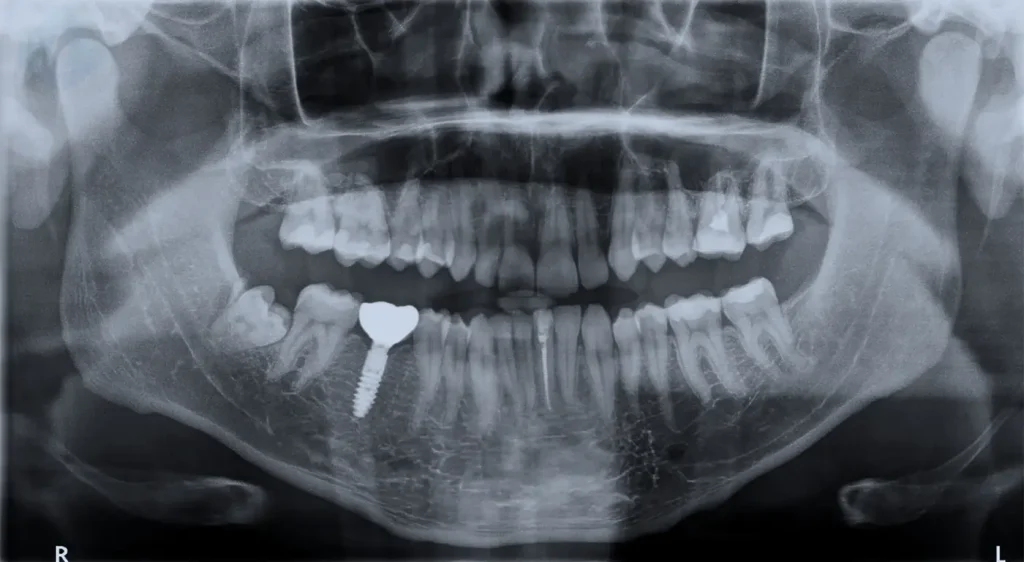

“I was eager to get my tooth back immediately. However, Dr. Carranza explained why waiting for the bone to fuse was critical. He showed me the X-rays. The education I received at Smile Design NJ was unmatched. Now, three years later, my implant feels rock solid. It was worth the wait.” – Michael T., Westfield, NJ.

Clinical Verification

During follow-up visits, we test the stability. We also take digital imaging. Radiographs should show bone growing tightly against the metal threads. Furthermore, the gum tissue should appear pink and healthy. No signs of infection should be present.